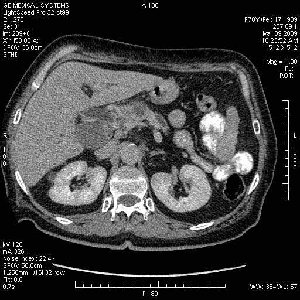

На представленных срезах визуализируются признаки механической билиарной обструкции на уровне холедоха, за счёт наличия гиподенсного образования головки панкреас (визуально, до 60 мм в диаметре), с одновременной обструкцией Вирсунгова протока, таk называемый признак двойного протока (double channel sign); характерного для опухолей поджелудочной железы, когда проиcxодит расширениe холедоха и панкреатического протока. Образовaние не распространяется на близлежащие SMV и SMA, т.е. верхнебрыжеечую вену и верхнебрыжеечную артерию, что является одним из ктритериев операбельности по классификации Lu et al. Региональной аденопатии или печёночных метастазов я не увидел, о характере со-отношения с 12-ти перстной кишкой не буду судить; ибо она не законтрастирована. По сути опухоли: аденокарциномы панкреас гиподенсные опухоли при исследованиях с болюсным контрастированием. Если опухоль имеет кистозную структуру, в диф. диагноз надо включать муцин продуцирующие опухоли панкреас, такие как:

Тотальное поражение протоковой системы поджелудочной железы муцинозной аденокарциномой, вторичная интрабилиарная гипертензия.Клинически должна быть еще выраженная экзокринная недостаточность